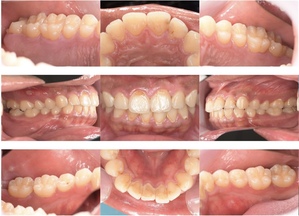

症例4

before

症例

after

抜歯前

抜歯後

基本情報

年齢・性別 26歳・男性

主訴 主訴:左下親知らず痛い

治療部位:左下8番

治療内容 ・左下8番埋伏抜歯

〈歯周病治療〉

①検査、資料取り(歯周ポケット検査、レントゲン14枚法、口腔内写真)、染めだし、歯磨き指導

②歯肉縁上の歯石除去、歯磨き指導、確認

③歯肉縁下の歯石除去(SRP)

④再評価

⑤メインテナンス

(2024年8月現在)

治療期間 約1ヶ月

治療費 合計:19,950円

〈内訳〉(全て保険診療3割負担)

①初診検査、左下8番埋伏抜歯:10,620円

②染めだし・歯磨き指導:1,110円

③歯磨き指導、確認・縁上歯石除去:2,830円

④縁下歯石除去(SRP)×2回:1,680円(×2回)

⑤再評価(歯周精密検査)・歯磨き指導:2,030円

リスク・副作用 ・歯石除去後、個人差はありますが1週間程度、歯を磨くといつもより出血することがあります。

・治療の結果、腫れていた歯ぐきが引き締まることで、歯ぐきが下がったように見えます。

下がった訳ではなく、本来の歯ぐきの位置に戻ったことによる見た目の変化です。

・歯ぐきが引き締まることにより、歯面が露出し知覚過敏の症状がでることがあります。

治療方針 左下の親知らずが痛いとのことでご来院された患者さまです。

親知らず周囲は汚れが落としきれておらず、歯ぐきが炎症を起こしている状態でした。

当日抜歯を希望されていたので、麻酔を効かせてから三次元的なレントゲン写真(CT)撮影し、抜歯を行いました。

その後、全顎的に歯石付着、歯ぐきの炎症が見られたので歯周病治療をその他の治療と並行して行っていきました。

特記事項 ・歯科受診約4年ぶり

・喫煙歴無し

・右下、左上の親知らずも抜歯済み

・コーヒー常飲

担当者所見 初診時は歯ブラシの交換時期を把握していなかった患者さまが歯ブラシを新しくしてから約1ヶ月後自分から歯ブラシを変えたことを教えてくださいました。

歯周病治療を進めていくうちに、患者さまの口腔内への意識が高まっていて治療が良い方向に進んでいきました。

歯周基本治療とセルフケアで歯ぐきの炎症や出血は初診時より大分改善されましたが、出血率を0%まで減らしていけるように今後は定期的な検診で歯ブラシの当て方や経過を患者さまと一緒に確認していこうと思います。

症例5

歯周病検査(治療前)

歯周病検査(治療後)

レントゲン写真

年齢・性別 32歳・男性

主訴 主訴:歯ぐきから出血する

治療部位:全顎

治療内容 「全顎」

歯周基本治療(歯周精密検査、スケーリング、OHI、SRP)

治療期間 約3ヶ月

治療費 歯周基本検査:約600円(保険診療3割負担)

スケーリング、OHI:約2,000円(保険診療3割負担)×2回

SRP、OHI:約1,500円(保険診療3割負担)×4回

歯周精密検査:約1,200円(保険診療3割負担)×2回

合計金額13,000円

(2025年2月現在)

リスク・副作用 歯石を取った後に、歯がしみることがあります。

治療方針 ①検査

レントゲン、口腔内写真を撮影して、歯や歯周組織の状態を確認します。

また、歯周病の検査で歯周ポケットの深さや出血の有無を確認します。

②スケーリング、OHI(口腔衛生指導)

スケーリングをして歯の表面の歯石を除去します。

また、正しい歯磨きの仕方や、フロスの通し方を一緒に確認します。

③歯周精密検査

前回歯石除去と歯磨き指導を行なった結果、歯ぐきの状態がどれぐらい改善したか検査します。

④SRP

歯ぐきの内側についてる歯石を除去します。

⑤歯周精密検査

SRP後、歯周病が改善されたか、検査します。

歯周ポケットが4ミリ以上の部位は、再度SRPを行います。

今回は歯周病の状態が安定したため、3ヶ月おきの定期検診で歯周病の再発や進行を防ぎます。

特記事項 歯周精密検査について:

・歯周ポケットが4ミリ以上ある場合は歯周病で、3ミリ以下は健康な歯ぐきです。

・出血の有無で炎症があるか確認します。

・磨き残しがある部分を確認して記録します。

担当者所見 初診時は、写真を見て分かるように、歯ぐきが赤く腫れていました。

また、歯周病の検査では、全体的に歯と歯の間の部分の歯周ポケットが4ミリあり、全体の約81%から出血が認められました。

出血量も多く、歯ぐきに触れた瞬間に出血しました。

レントゲンで骨のレベルがしっかりとあることが確認できました。

そのため、ご自身で正しい歯磨きを継続することで改善すると考えました。

歯周基本治療を経て、再度検査した結果、歯周ポケットはほぼ3ミリ以下に改善しました。左下7番の残存した歯周ポケットは、隣の親知らずを抜いたため経過観察します。

出血率は約4%まで改善し、出血量も点状で少なくなりました。

今後は右上2番、右下3番の歯ぐきの発赤の改善と、出血率0%を目指して、定期検診でメンテナンスしていきます。